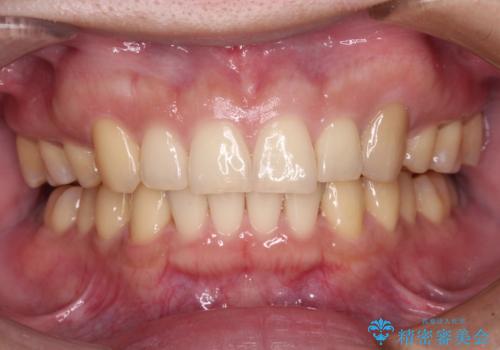

下顎前歯が隠れて突出した口元 ワイヤー装置での抜歯矯正

- 前歯のデコボコと口元の突出感を気にして来院された患者様です。

骨格的な左右差がありましたが、何とか当初予定していた期間で、左右対称の咬み合わせに仕上げることができました。